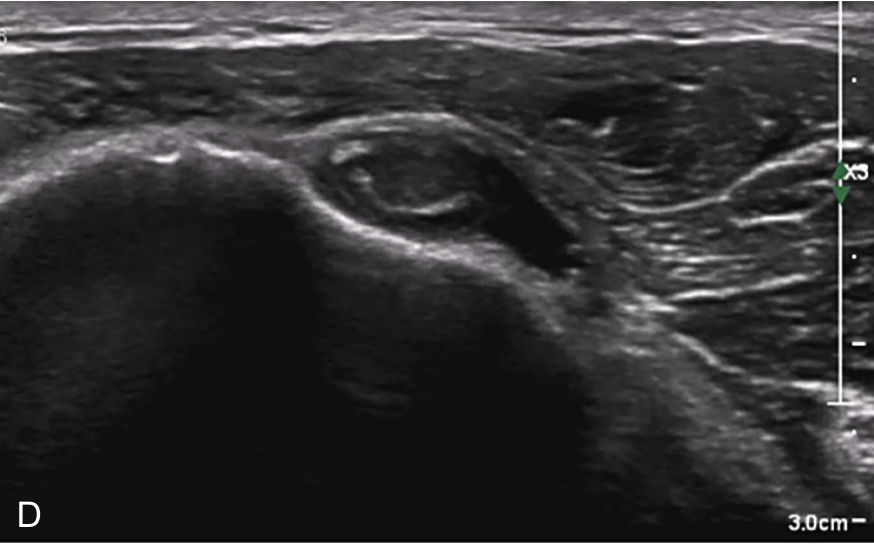

▲ 图2-3-4 超声引导下肱二头肌长头腱鞘介入治疗超声图(一)

A.二维超声:肱二头肌腱鞘内少量积液及滑膜增生;B.超声多普勒:肱二头肌腱鞘内及周围血流较丰富;C.平面内进针法,针尖进入肱二头肌长头腱鞘内;D注射治疗后腱鞘液体增多